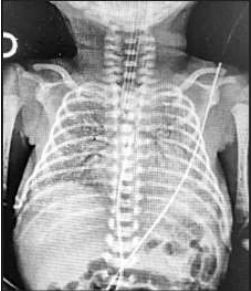

RN nasceu de parto vaginal, com APGAR 5 e 6, apresentando desconforto respiratório de imediato, caracterizado por gemência, tiragem subcostal e taquipneia. A idade gestacional pela DUM foi de 31 semanas. RN foi levado à UTI neonatal, com piora importante do desconforto respiratório, necessitando de intubação orotraqueal. Neonatologista solicitou RX de tórax (imagem abaixo). Genitora relatou perda de líquido vaginal um dia antes do parto, porém, como foi em pequena quantidade e não teve contrações, decidiu ficar em casa. Somente foi à maternidade, 20 horas após a ruptura das membranas, em função da intensidade forte e frequente das contrações. RN nasceu cerca de duas horas após admissão da gestante na maternidade. Dados pré-natais: Gesta IV/ Aborto II. O cartão da gestante mostrou apenas quatro consultas, com exames realizados somente no primeiro trimestre (todos normais).

Enunciado 4043133-1

I. Uma das hipóteses diagnósticas para esse RN é de pneumonia pelo Streptococcus do grupo B, sendo indicada antibioticoterapia com penicilina cristalina e gentamicina.

II. A prematuridade e o padrão radiológico tornam a Síndrome do Desconforto Respiratório um dos principais diagnósticos desse paciente.

III. O RN deverá receber uma dose de surfactante exógeno o mais rapidamente possível; estudos recentes mostram a ineficácia de doses subsequentes de surfactante, além do elevado risco de pneumotórax.

IV. A hipóxia perinatal, prematuridade e ausência de corticoide pré-natal são fatores de risco para uma produção insuficiente de surfactante pelos pneumócitos tipo I ainda na vida intrauterina.